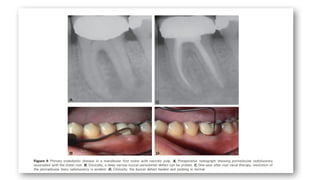

PRIMARY ENDODONTIC DISEASE

 A deep solitary pocket in the absence of periodontal disease may indicate

the presence of a lesion of endodontic origin.

 For diagnosis purposes, a gutta-percha cone, or another tracking

instrument, should be inserted into the sinus tract and radiographs taken.

This will determine the origin of the lesion.

 A sulcular pocket of endodontic origin is typically very narrow compared

to a pocket of periodontal origin. A similar condition occurs where drainage

from the apex of a molar extends coronally into the furcation area

 Primary endodontic lesions usually heal following root canal treatment.

The sinus tract extending into the gingival sulcus or furcation area quickly

heals once the affected pulp has been removed and the root canals cleaned,

shaped, and obturated